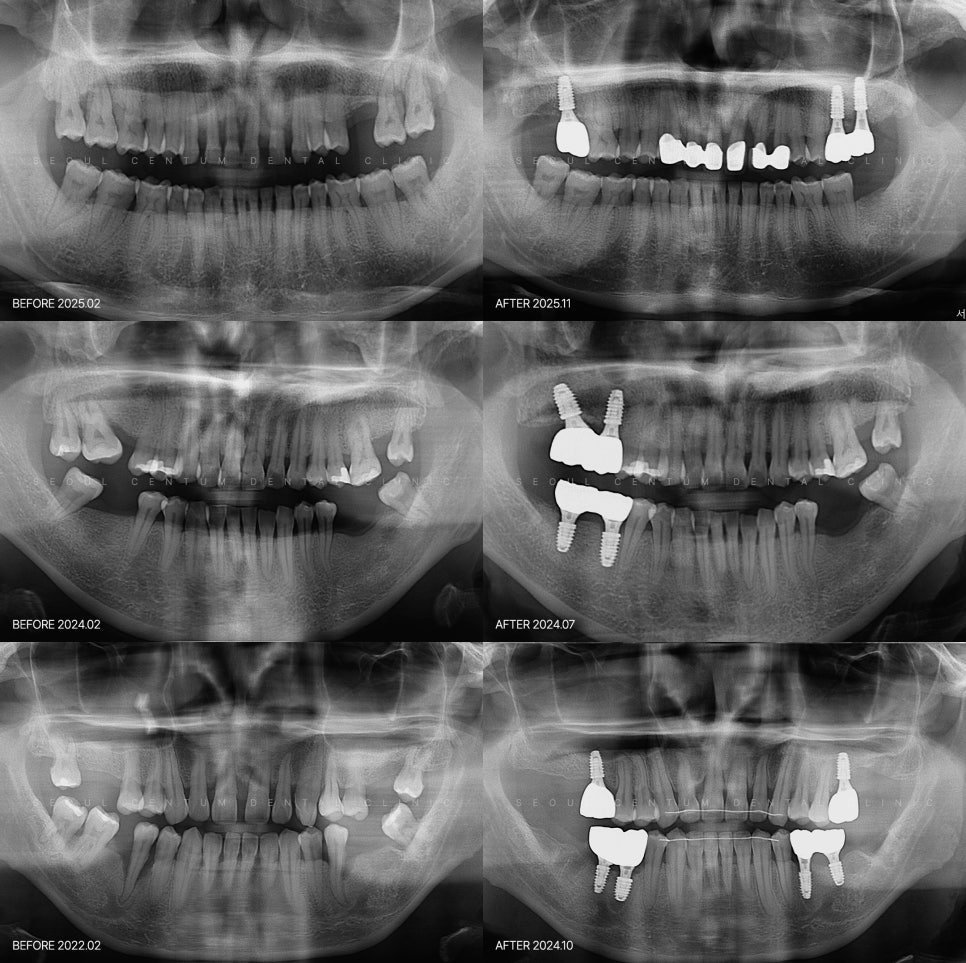

치주염으로 사랑니 발치 후 옆 치아에 임플란트를 권유받았을 때는 문제의 정도가 심해 발치하고 바로 옆 치아까지 동일하게 하면서 임플란트도 해야 한다는 말을 들을 수 있어요. 갑작스럽게 두 개 이상의 치아 발치 이야기를 듣게 되면 적절한 조치인지 고민될 수밖에 없겠는데요. 임플란트 치주염 옆자리에 권유받았다면 필요한지...

옆 치아까지 해야 하는지는 별도의 판단 필요

사랑니 발치 후 옆 치아까지 발치를

권유받는 경우가 있어요.

통증이 없으며 치아가 올곧게 유지되고 있다면

발치라는 조치가 당장 필요한 상황은

아닐 가능성이 있습니다.

발치 후 임플란트가 필요한 시점은?

잇몸뼈 소실이 매우 심하거나

치아가 심하게 흔들리는 경우라면

이러한 결단이 필요할 수 있습니다.

치근을 충분히 지지하지 못하면

장기적인 유지가 어려울 수 있거든요.